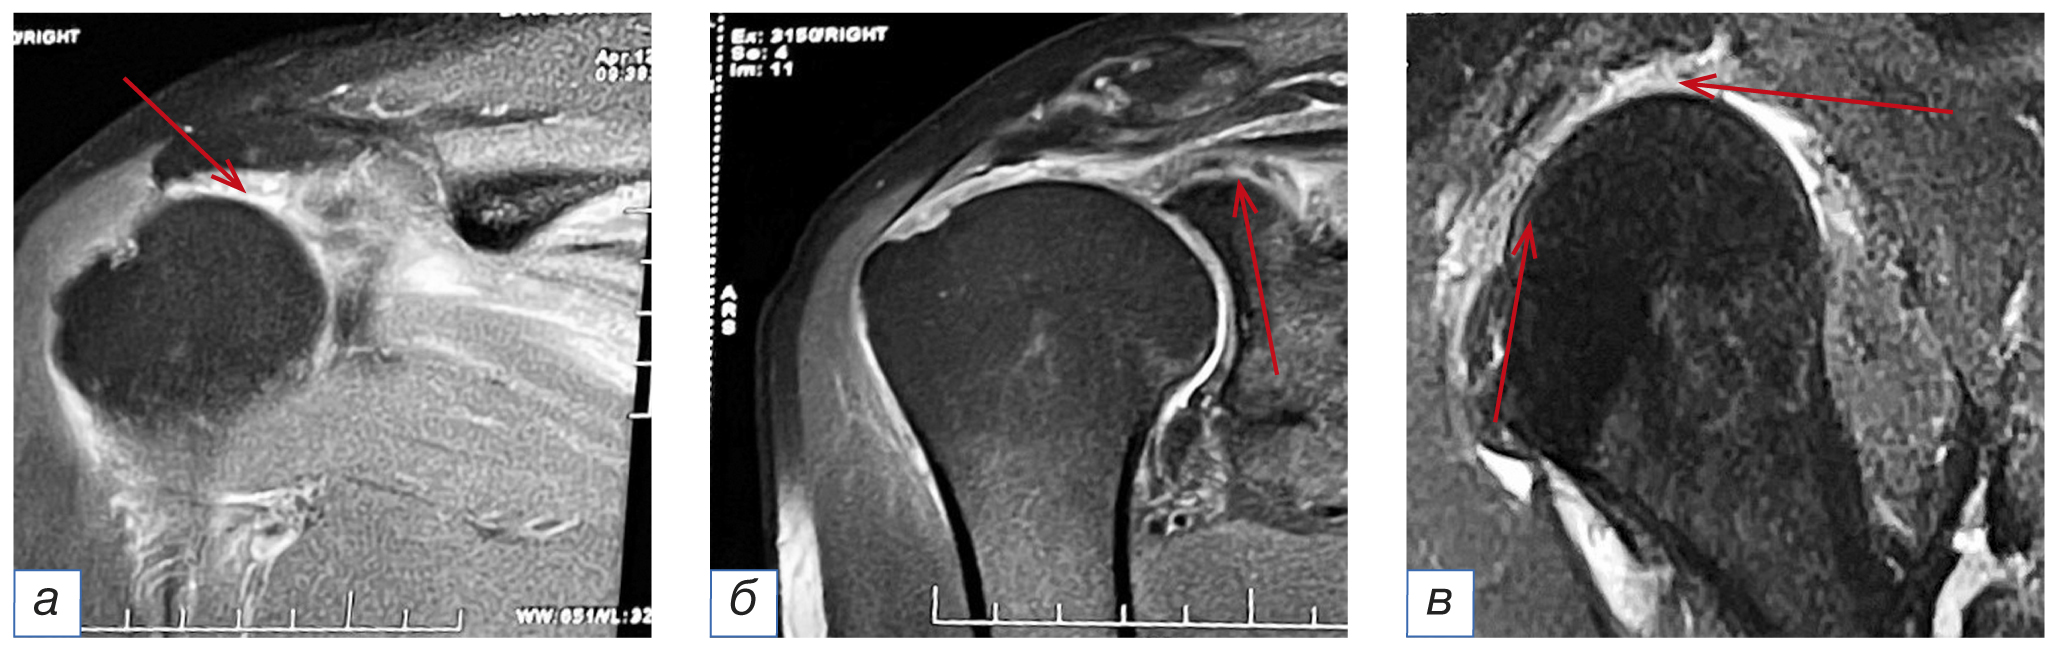

По данным магнитно-резонансной томографии (МРТ) правого плечевого сустава: заострение суставных поверхностей акромиально-ключичного и плечелопаточного сочленений, неравномерное истончение суставного хряща, суставных щелей. Имеются признаки переднего подвывиха головки плечевой кости. Расстояние между акромионом и головкой плечевой кости до 0,7 см. Сухожилия надостной и подостной мышц разволокнены, имеют неоднородную структуру. МРТ-картина разрыва сухожилий надостной и подостной мышц, признаки подвывиха головки плечевой кости. Деформирующий артроз плечевого сустава (рис. 3).

Рис. 3. Магнитно-резонансная томография правого плечевого сустава: а — подвывих головки правой плечевой кости (стрелка); б — ретракция сухожилия надостной мышцы (стрелка), III стадия по Patte; в — дефект сухожилий надостной и подостной мышц (стрелки).

Fig. 3. Magnetic resonance imaging of the right shoulder joint: а — subluxation of the head of the right humerus (arrow); б — retraction of the tendon of the supraspinatus muscle (arrow), stage III according to Patte; в — defect of the tendons of the supraspinatus and subacute muscles (arrows).